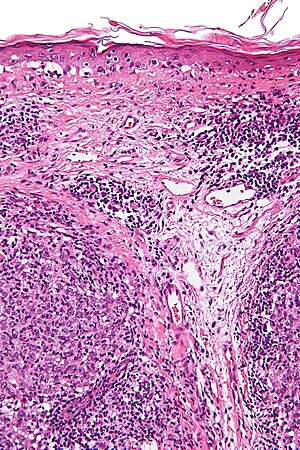

Lymphoepithelioma-like carcinoma. H&E stain. | |

| LM | clusters of cohesive squamoid cells with abundant dense cytoplasm, central nuclei +/- small/indistinct nucleoli, surrounded by a prominent lymphoid component |

- Clusters of cohesive squamoid cells with:

- Abundant dense cytoplasm.

- Central nuclei +/- small/indistinct nucleoli.

- Surrounded by a prominent lymphoid component - key feature.